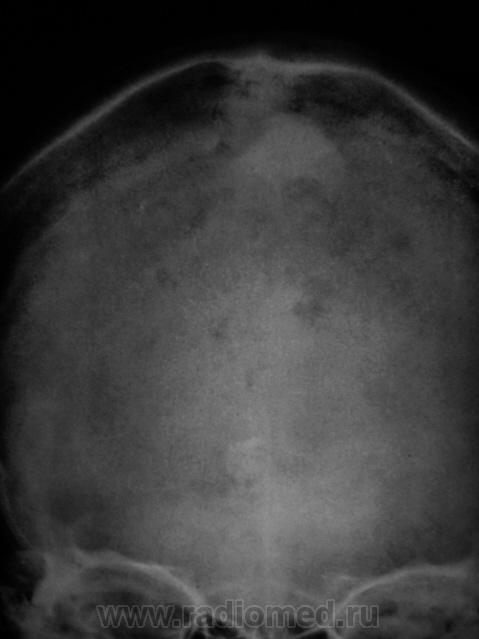

Пациентка направлена на рентгенографию черепа.

Какие будут мнения уважаемые коллеги?

Диплоические каналы и бухты. Пахионовы ямки. Брегма заросла как-то не так.

А, как быть с теми двумя "плямами" (прямая проекция), одна больше другая меньше по размерам.

Suspicio Ca dura mater.

Я конечно с головой не дружу. Но мне каца , на боковой рентгенограмме,что имеет место эндокраниальный гиперостоз лобно-теменной области с разрушением внутренней пластинки.Сиречь-опухоль.

Этот случай, в какой-то степени, аналогичен случаю, выставленному Побединским Михаилом Александровичем - "округлая тень". Это "тенеобразование", на фоне чешуи лобной кости вызвано наличием значительных размеров родинок но коже лба, и частично, волосистой части головы.